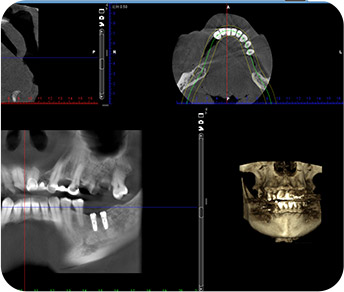

從方案設計、種牙手術、牙冠製作、戴牙全程可視化,术前可以充分采集患者数据,预先设计种植方案并制作辅助配件,实现“以结果为导向、全程可视化预期、风险可预见规避”,每個環節公開透明,所見即所得。

從方案設計、種牙手術、牙冠製作戴牙全程可視化,每個環節公開透明所見即所得。